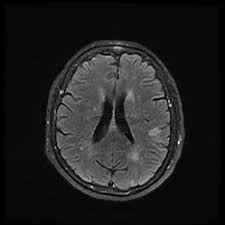

MRI Brain Stroke Protocol is a series of specialised imaging techniques that uses magnetic resonance imaging (MRI) to examine the brain. This detailed imagery is very beneficial in diagnosing strokes, helping doctors identify the presence, location and extent of the stroke.

MRI Brain Stroke Protocol is performed to help in diagnosing issues like:

- Ischemic strokes.

- Edema and extent of the stroke.

- Abnormalities like tumours or vascular malformations which can be similar to stroke symptoms.

- Brain injury areas and swellings.

- Artery patency, stenosis or occlusion.